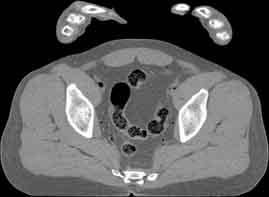

Visible Human male: Sectio transversalis 1844

CT